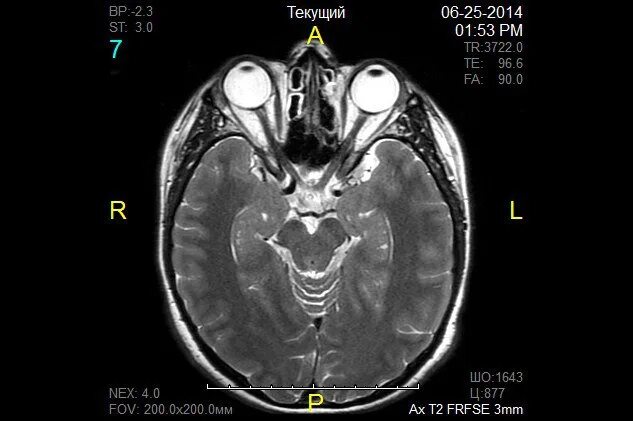

Мрт орбит и зрительных нервов